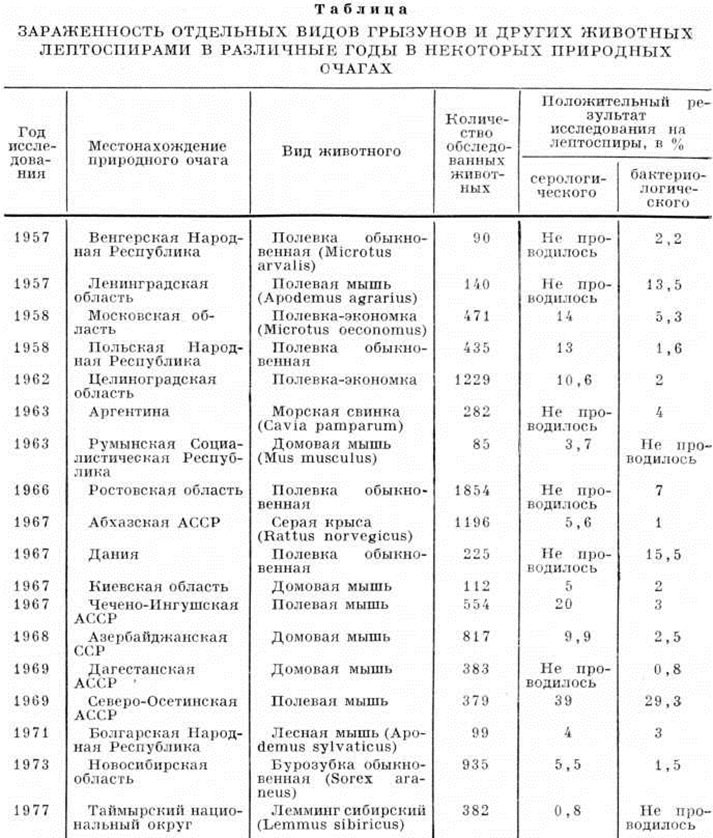

Источником возбудителей в природных очагах являются млекопитающие отрядов грызунов, насекомоядных, сумчатых, парнокопытных и хищных, в меньшей степени пресмыкающиеся, земноводные и птицы. Наибольшее значение имеют грызуны из семейство хомякообразных (полёвки, ондатры, хомячки и другие) и мышеобразных (мыши, крысы). Заражённость Лептоспироз этих зверьков в различных очагах зависит от их численности, возраста, времени года, характера местности и другие и колеблется от нескольких процентов до 50—60% и выше. Высокая заражённость Лептоспироз в ряде европейских и отечественных природных очагов выявлена у полёвок (полёвка-экономка, обыкновенная полёвка, дальневосточная полёвка и другие).

Заражённость грызунов и других животных в природных очагах Лептоспироз представлена в таблице.